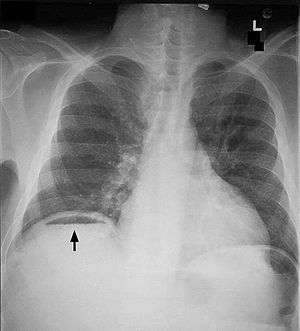

Pneumoperitoneum is pneumatosis (abnormal presence of air or other gas) in the peritoneal cavity, a potential space within the abdominal cavity. When present, it can often be seen on radiography, but small amounts are often missed, and CT scan is nowadays regarded as a criterion standard in the assessment of a pneumoperitoneum.[1] CT can visualize quantities as small as 5 cm³ of air or gas. The most common cause is a perforated abdominal viscus, generally a perforated peptic ulcer, although any part of the bowel may perforate from a benign ulcer, tumor or abdominal trauma. A perforated appendix seldom causes a pneumoperitoneum.

Subphrenic abscess, bowel interposed between diaphragm and liver (Chilaiditi syndrome), and linear atelectasis at the base of the lungs can simulate free air under the diaphragm on a chest X-ray.